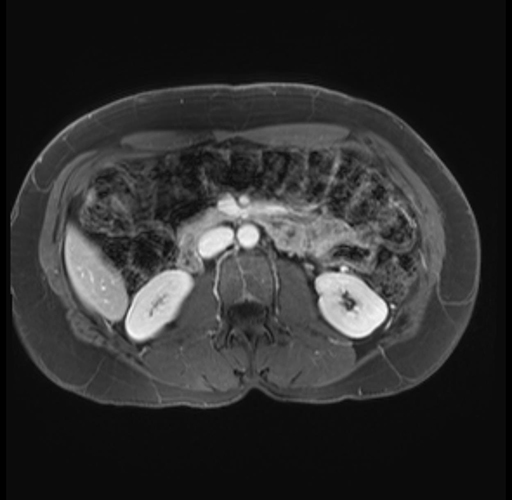

Imaging Analysis

Look through the patient's CT scan to identify any areas of concern for the necessary procedure.

Based on your CT findings, which issue(s) are present and would give reason for "planned slowing down moment(s)" in this case?